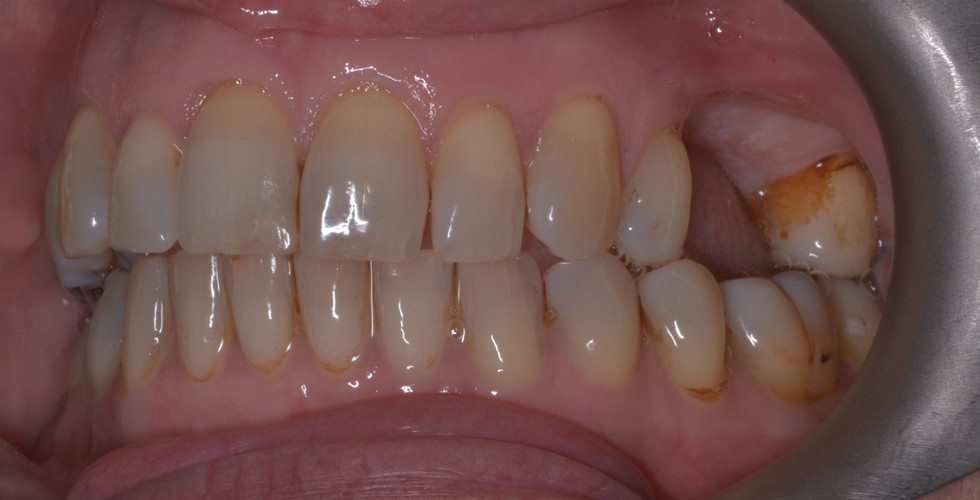

This lovely lady was already a patient of the practice when I saw her. She'd had a gap at the upper left for some time, ever since the first molar had cracked in half. She was also starting to show signs of a crack in the second molar (UL7) so I surmised she's got a pretty strong bite!

Here's a photo of her teeth with the gap.